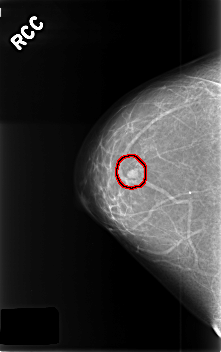

C_0382_1.RIGHT_CC

RIGHT_CC LINES 4568 PIXELS_PER_LINE 2872 BITS_PER_PIXEL 12 RESOLUTION 50 OVERLAY

FILE: C_0382_1.RIGHT_CC.OVERLAY

TOTAL_ABNORMALITIES 1

ABNORMALITY 1

LESION_TYPE MASS SHAPE OVAL MARGINS CIRCUMSCRIBED

ASSESSMENT 3

SUBTLETY 5

PATHOLOGY BENIGN

TOTAL_OUTLINES 1

BOUNDARY